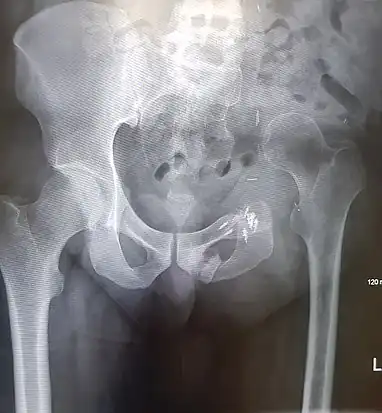

- An x-ray of the same pelvis taken eighteen months after surgery highlighting the femur migration to its final resting place.